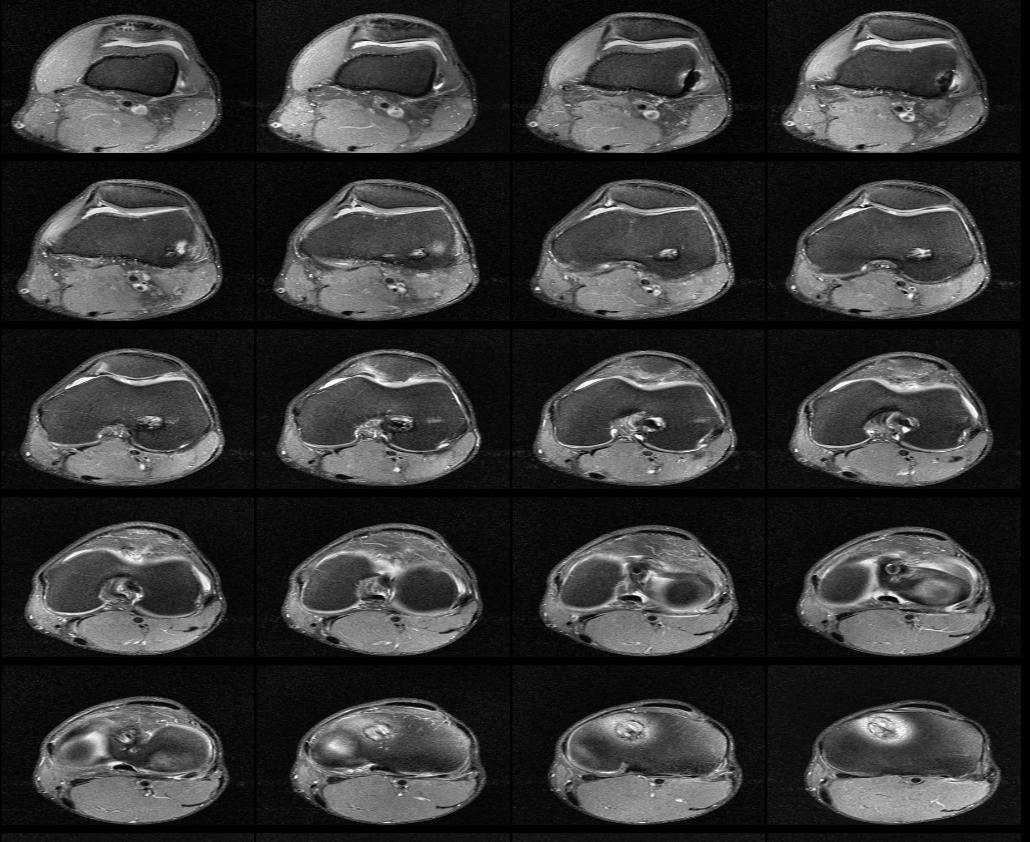

무릎 십자인대 재건술 후 약8년이 지난 지금 mri를 찍었습니다. 판독부탁드립니다ㅠㅠ

약 8년전 무릎 전방십자인대 재건술을 했는데 , 운동관련 직종이다 보니 , 운동을 많이 합니다.

최근들어 무릎에 불편한 통증이 있어 mri를 찍었는데 ,

활막염이라는 말만 들었는데 , 여러 선생님들의 의견을 듣고 싶어 사진올립니다. 판독해주시면 정말 너무너무

안녕하세요. 채홍석 의사입니다. MRI 퀄리티가 나빠서 판독은 어렵겠네요.